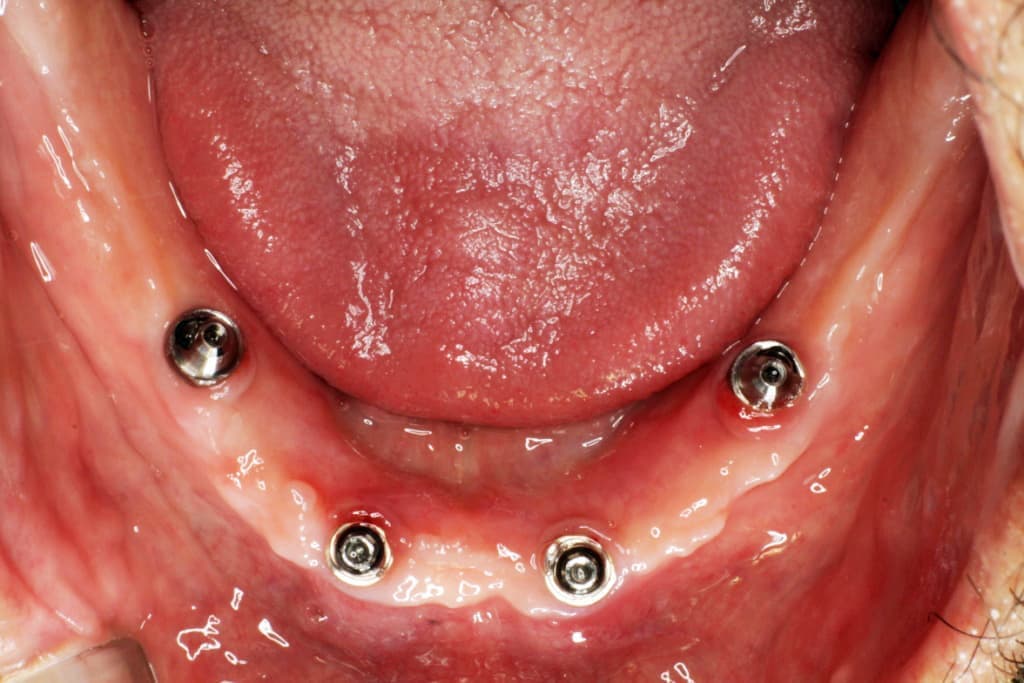

オールオン4は、奥のインプラントを骨のある部分へ斜めに埋め込み力を広く均等に分配することにより、最小4本のインプラントで全ての人工歯を支えることができる術式です。

手術による身体的負担や費用の負担なども最小限に抑えることができます。

※上顎の場合は4本で支えきれない事があり、インプラントの本数追加が必要な場合もあります。

※顎の骨の状態によっては下顎であってもインプラントの本数追加が必要な場合もあります。

被せ物はチタンフレームに組んだジルコニアを使用いたします。